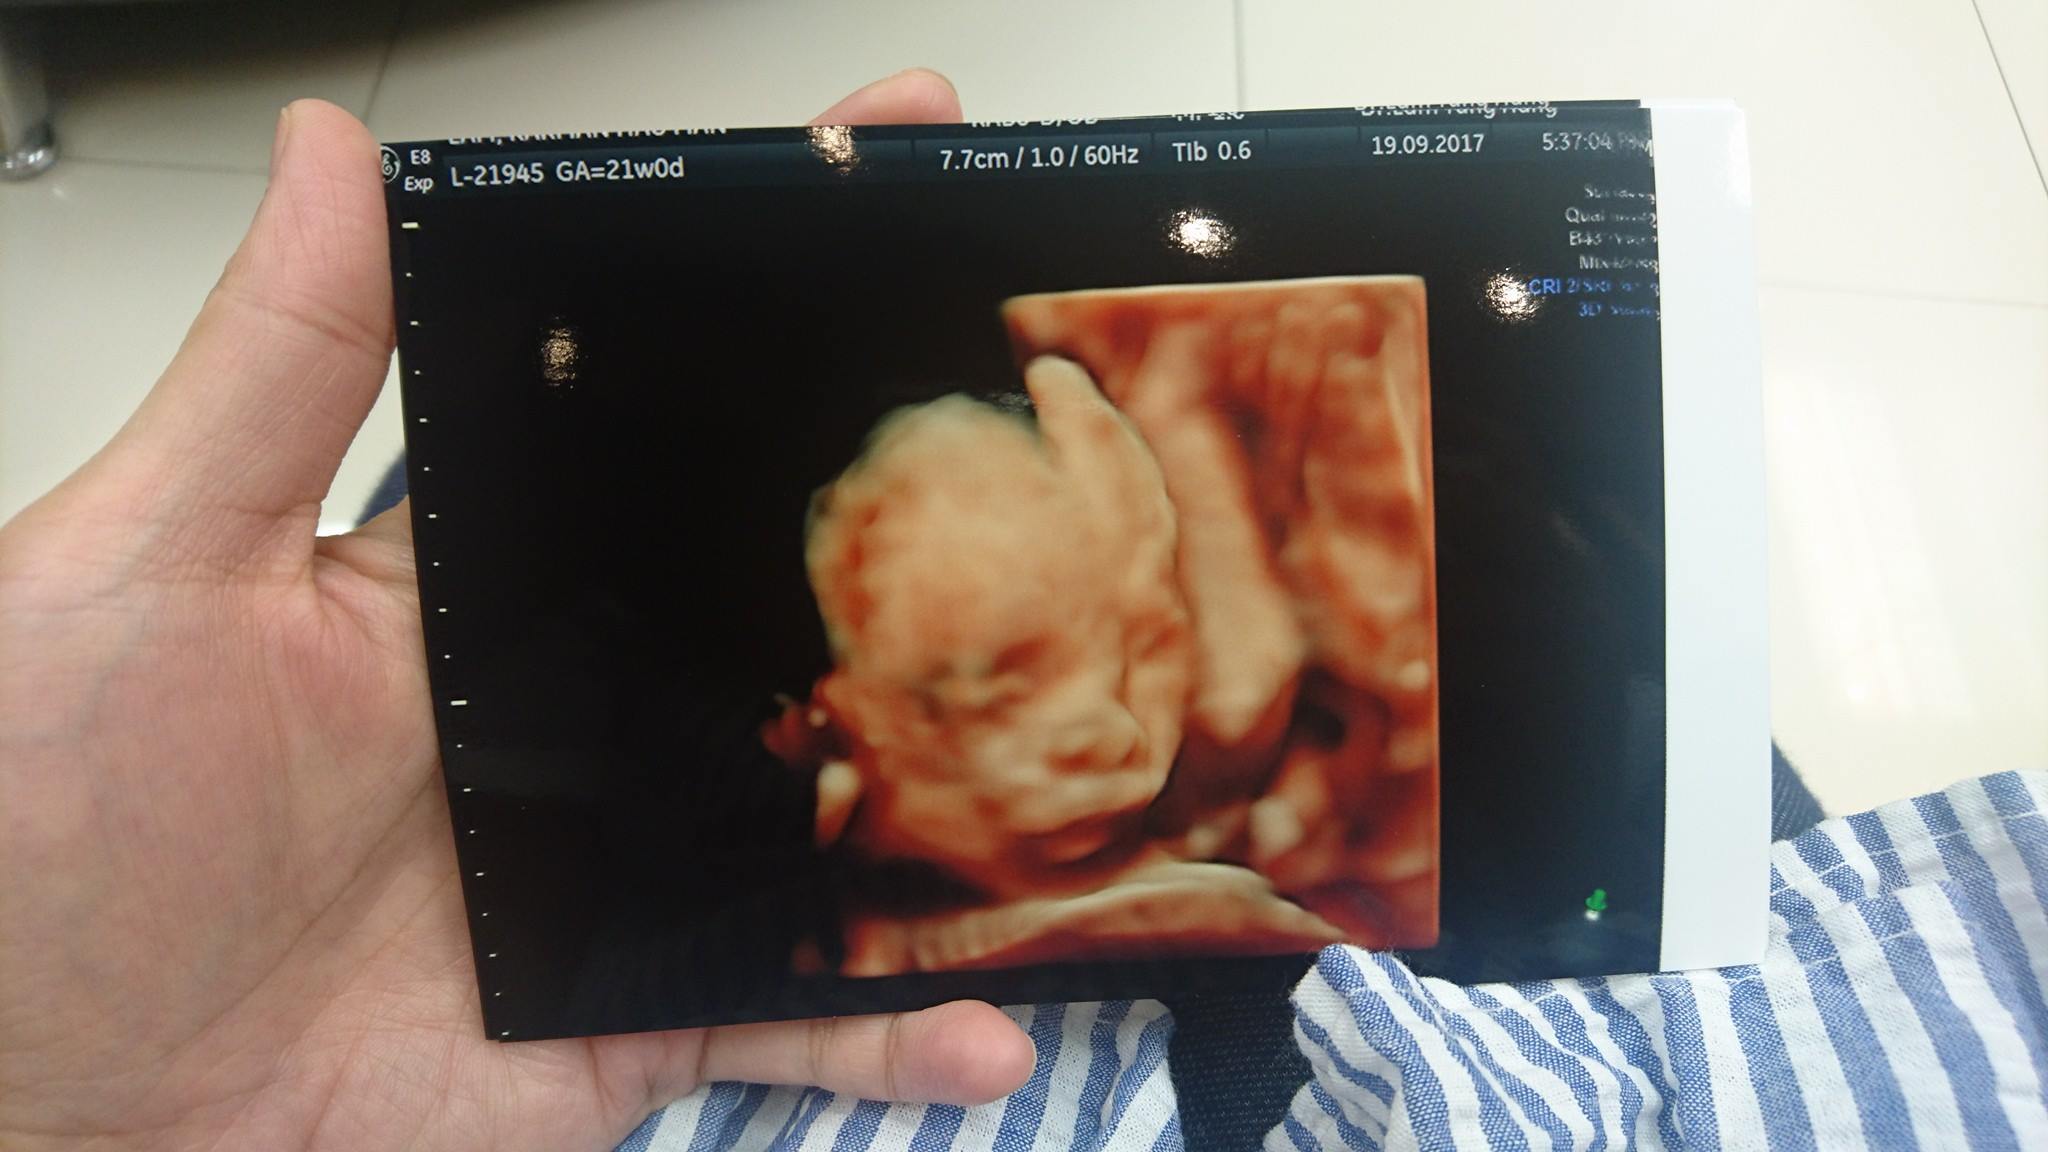

TBB新劇《BB來了》開播未夠一星期,由李佳芯同黎諾懿飾演嘅新手爸媽盡講「血淚史」,由懷孕去到育兒超貼地,播出未夠一星期已經成功吸引一班年輕媽媽熱烈討論。